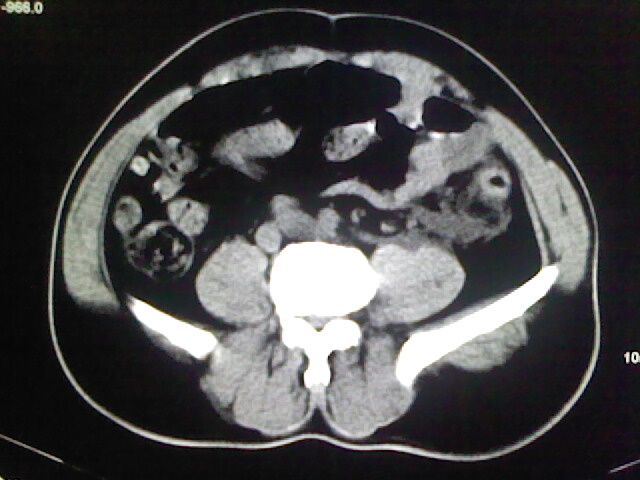

以下是引用zsl6918在2009-2-7 7:29:00的发言:[br]请提供介入的方式方法,肾及输尿管改变考虑与介入损伤有关,漏了,尿液外渗。

以下是引用余辉在2009-2-7 8:27:00的发言:[br]可能是硬化剂烧穿囊壁进入肾盂输尿管了,尿漏。不除外介入或碎石术后合并感染[br]患者术后怀疑结石,接着就碎石了?就怀疑没有确诊吗?碎石用的什么方法?气压弹道还是体外超声?如果这样的话责任人都难找

以下是引用随光逐影在2009-2-7 8:46:00的发言:[br]支持3楼意见。[br]另:不排除左肾及肾周感染可能。